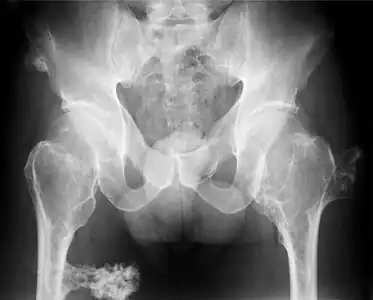

multiple osteochondromas at the pelvis -